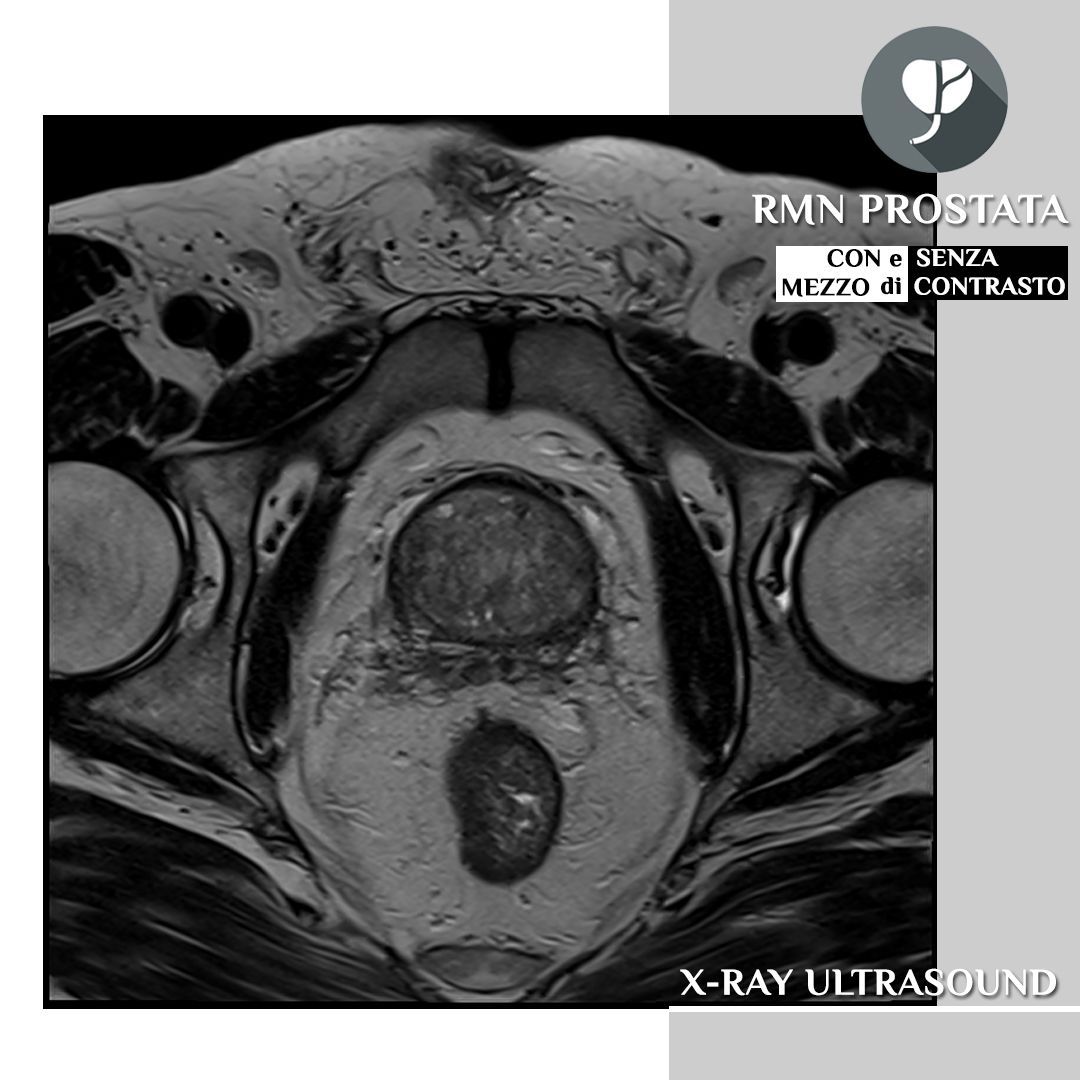

Diagnosi di patologie complesse: la risonanza Magnetom Altea è particolarmente indicata per la diagnosi di patologie complesse di diverse aree del corpo, tra cui:

- Pelvico: prostata, vescica, utero, ovaie

- Multiparametrico della prostata: valutazione del cancro alla prostata